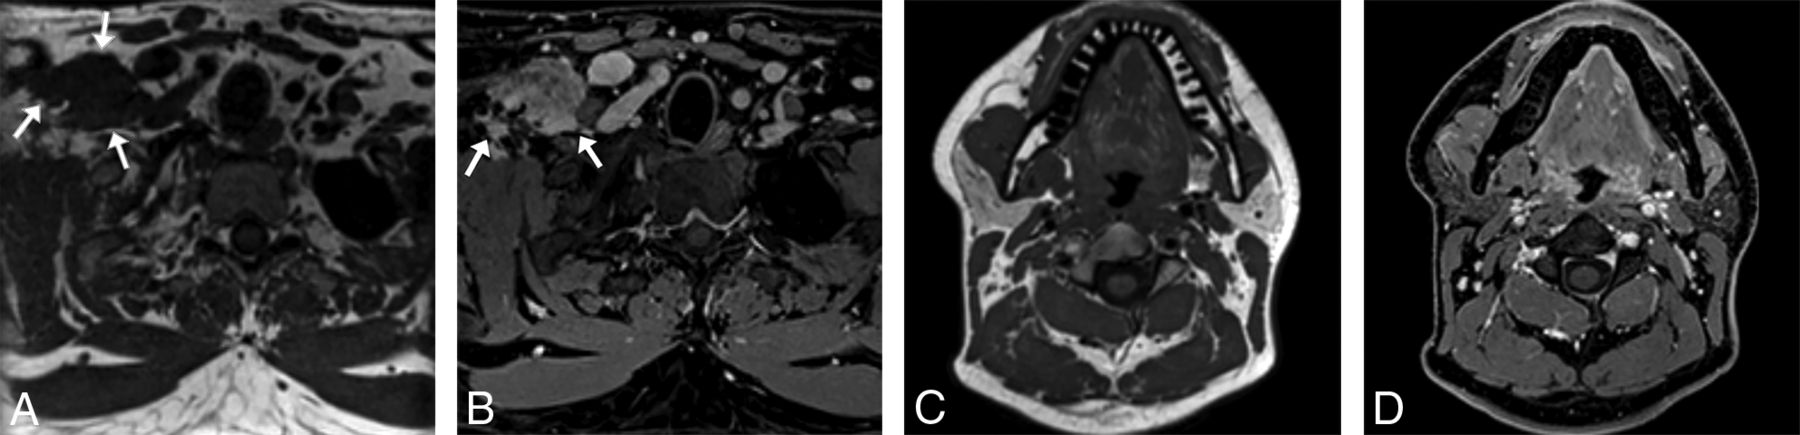

For the nonfocal whole-neck protocol, we acquired data in the sagittal plane, which minimizes the scan range and eliminates the potential for wrap artifacts from the body and vertex scalp. Given that this protocol is used for identification of gross soft-tissue abnormalities without the necessity for finer spatial detail, we acquired it at 1-mm isotropic resolution. However, even with 1-mm3 voxels, this sequence can often more clearly show smaller lesions than in what we traditionally called high-resolution 2D acquisition images, which were submillimeter in-plane but with 3-mm or thicker section thickness. An example is provided in Fig 2 of images from a 92-year-old woman with a small focal preauricular metastasis of cutaneous squamous cell carcinoma invading the parotid gland.

A 92-year-old woman with squamous cell carcinoma. A, T1 SPACE sequence performed in the full-neck MR imaging protocol with 2.7-mm3 (1.4 mm isotropic) voxels during early optimization iterations reformatted into the axial plane clearly shows a cutaneous preauricular lesion (arrow) that is not visible due to volume averaging on the 2D T1-weighted image (B) with 1-mm3 (4 × 0.5× 0.5 mm) voxels. The T1 VIBE Dixon (C) reformatted image in the axial plane shows the associated infiltrating tumor into the parotid gland (arrow) to advantage compared with the 2D T1-weighted image (D) with spectral fat suppression. The case convinced us that the SPACE sequence was a reasonable alternative to the 2D standard-of-care and led us to improve the spatial resolution of the SPACE sequence. These images were obtained contemporaneously on a 3T Magnetom Vida system.